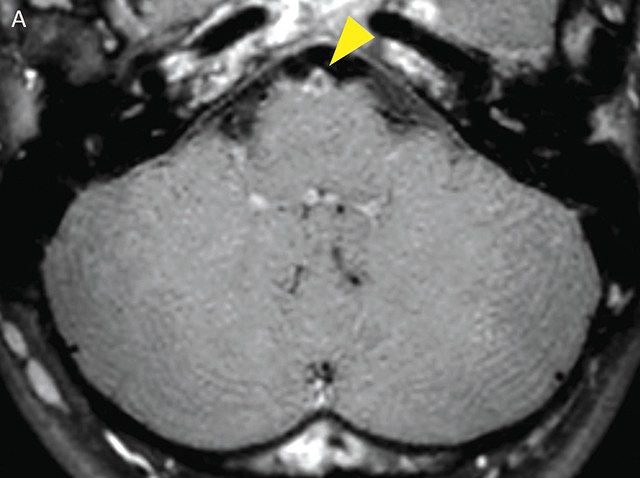

Teaching point: Meningovascular neurosyphilis is a cause of stroke in the young, and the diagnosis could be aided by black-blood MRI sequences.

教学要点:脑膜血管神经梅毒是导致年轻人中风的原因之一,黑血磁共振成像序列可以帮助诊断。